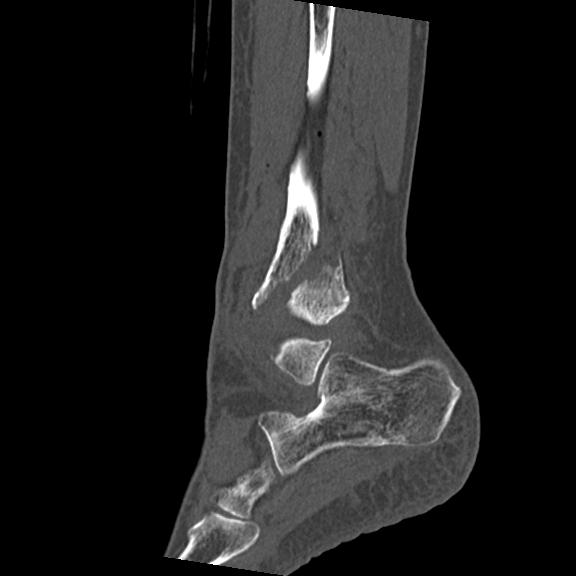

56476 8/28 4R 1/21 2R 左足関節 デジカメ写真 72歳女性 右足関節AS

102755 1/4 2R 1/15 2R 右足関節 68歳女性 右三果脱臼骨折